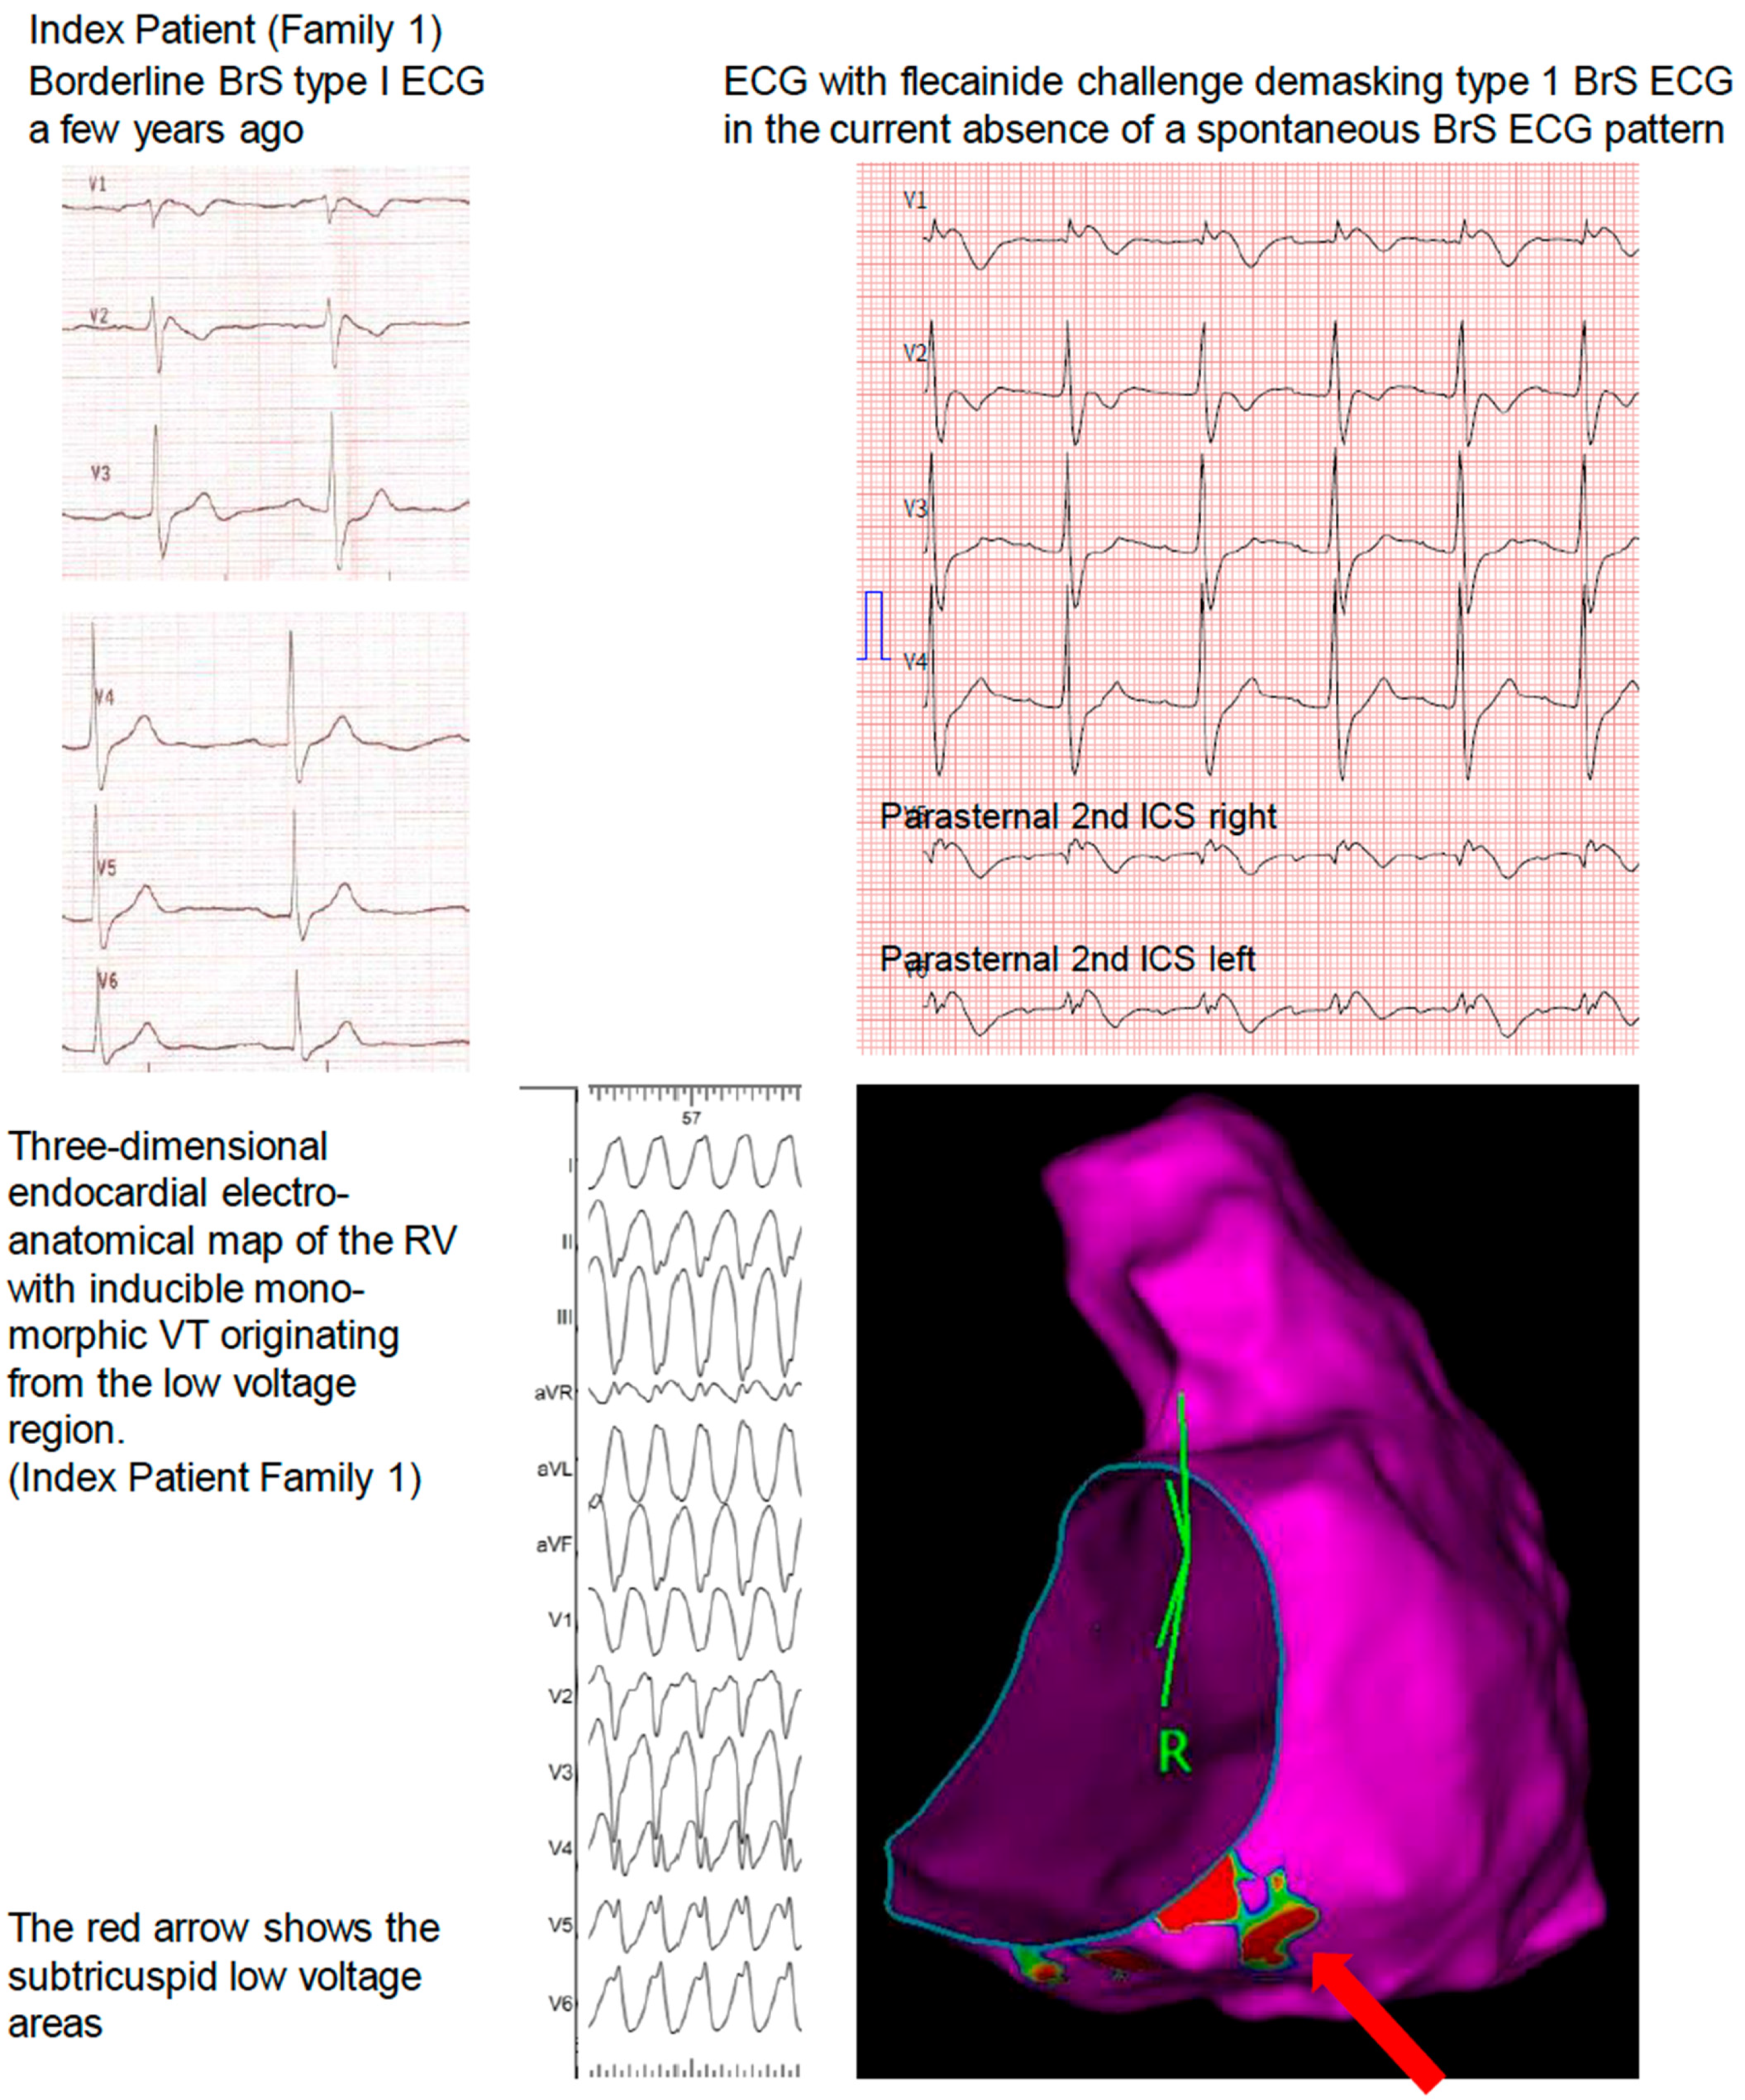

Electroanatomical Mapping in Family 1

3.1. Family 1